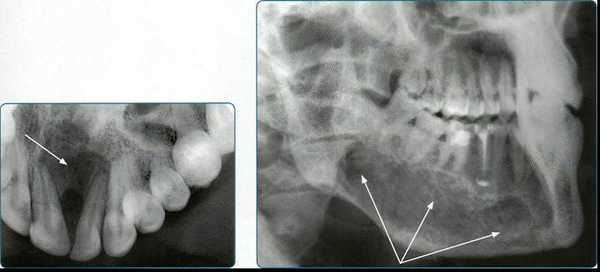

Ramamurthy и Matherene описывают ограниченность 2D изображений для определения MB2 каналов (Фото 1).

Фото 1: изображение MB2 в обоих первых молярах

Наиболее частым патологическим состоянием, затрагивающим зубы является воспалительные процессы пульпы и периапикальных областей. Технология КЛКТ теперь предоставляет клиницисту возможность обозревать нужную зону в трех различных плоскостях, тем самым получая 3D информацию. Поражения, заключенные в губчатом веществе кости с малым количеством или отсутствием кортикальной пластинки, на обычной пленке могут быть диагностированы с большим трудом. Lofthag-Hansen, Stavropoulos и Wenzel сравнили точность получаемых данных при КЛКТ с ограниченным FOV и обычными снимками.

Ученые сообщили, что КЛКТ предоставляет более точные диагностические данные (61%) по сравнения с цифровыми (39%) и обычными (44%) рентгенограммами. Но, несмотря на то, что данные КЛКТ являются более точными, исследователи не призывают к полному вытеснению обычной внутриротовой рентгенографии для выявления периапикальных изменений в обычной клинической практике из-за финансовой и вредностной составляющих. Estrela и коллеги предложили использовать периапикальные индексы, основанные на КЛКТ, для идентификации патологий (Фото 4-6).

Фото 4: Периапикальная киста в переднем сегменте нижней челюсти

А: 3D изображение, показывающее большую кистозную полость

B: Изображение секционного распила, показывающее утрату кортикальной пластинки

C: Аксиальный вид, демонстрирующий утрату кортикальной пластинки с лабиальной стороны и интактную пластинку с лингвальной.

Фото 5: Хронические периапикальные абсцессы около первого правого нижнего моляра

Фото 6: Поражение периодонтальных тканей около левого верхнего второго моляра